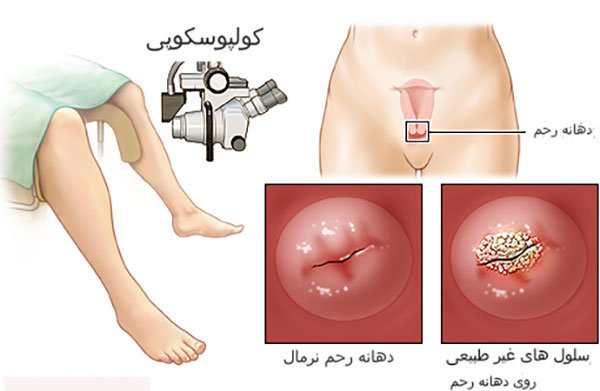

کولپوسکوپی روشی برای مشاهده دهانه رحم، واژن و ولوو یا فرج از طریق یک دستگاه بزرگنمایی خاص به نام کولپوسکوپ است. کولپوسکوپ می تواند نمای طبیعی را تا حد زیادی بزرگ کند. این معاینه به یک متخصص زنان و زایمان اجازه می دهد تا مشکلاتی که تنها با چشم غیر مسلح قابل مشاهده نیستند را پیدا کند.

کولپوسکوپی زمانی انجام می شود که نتایج آزمایش های غربالگری سرطان دهانه رحم یعنی همان تست پاپ اسمیر تغییرات غیر طبیعی در سلول های دهانه رحم را نشان دهد. کولپوسکوپی اطلاعات بیشتری در مورد سلول های غیر طبیعی ارائه می دهد. در صورت ابتلا به انواع خاصی از ویروس زگیل تناسلی یل پاپیلومای انسانی (HPV) کولپوسکوپی نیز انجام شود.

نحوه انجام کولپوسکوپی به اینصورت است که مانند معاینه لگن، شما روی تخت معاینه زنان یا تخت ژنیکولوژی به پشت دراز می کشید و پاهای خود را بر روی قسمت مربوط به پا که بالاتر قرار دارد و پاها را حمایت میکند قرار میدهید، سپس پزشک متخصص زنان شما از اسپکولوم برای جدا کردن دیواره های واژن استفاده می کند تا داخل واژن و دهانه رحم دیده شود. یک نور روشن هم جهت مشاهده دقیق تر به ناحیه تابیده می شود. دستگاه کولپوسکوپ درست خارج از ولوو یا فرج قرار می گیرد، منظور این است که این دستگاه وارد واژن شما نمی شود بلکه با باز شدن واژن از طریق اسپکولوم، به حفره واژن و دهانه رحم یعنی سرویکس شما از بیرون نگاه میکند و با دید میکروسکوپی از طریق لنزهایی که دارد تصویری با بزرگنمایی زیاد از این نواحی در اختیار پزشک متخصص زنان قرار میدهد تا تغییراتی که با چشم غیر مسلح قابل دیدن نیستند را ببیند.

کولپوسکوپی نتایج عادی نشان می دهد و هیچ تغییر غیرطبیعی در آزمایش پیدا نشده است.

و یا نتایج غیر طبیعی را نشان میدهد.